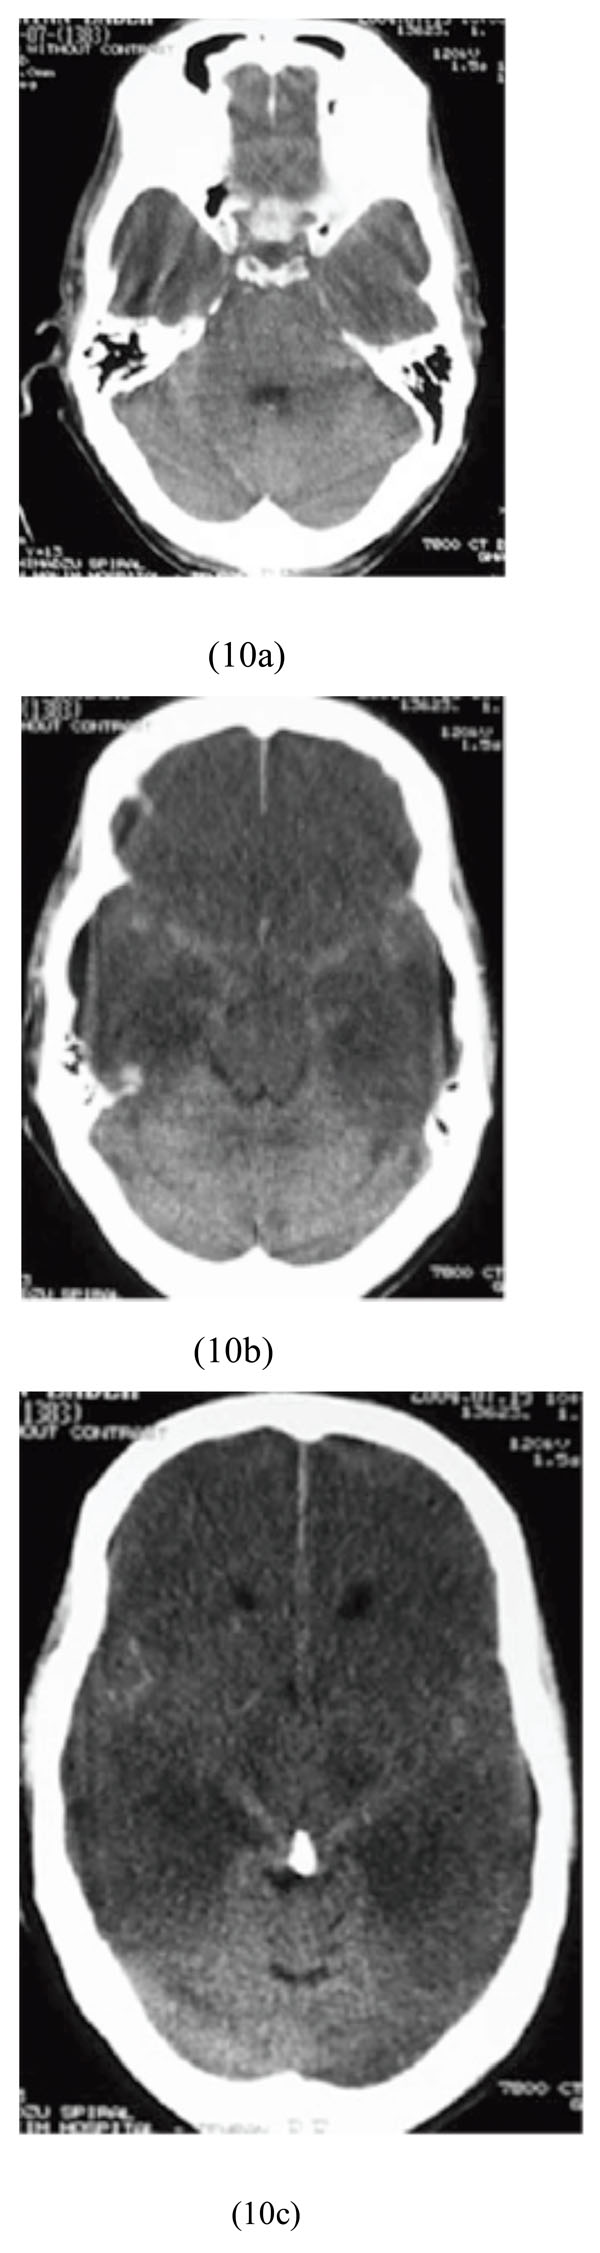

Case 10

A 20-year-old man, who decided to commit a suicide with insulin injection, was brought to our hospital in comatose state with a blood sugar level of 15 mg/dL. He was admitted and then treatment with intravenous glucose was initiated. Brain CT scan showed diffuse bilateral supratentorial cytotoxic edema and pseudo-subarachnoid hemorrhage sign (Figs. 10a-10c).

Diffuse bilateral supratentorial cytotoxic edema and pseudosubarachnoid hemorrhage sign after insulin injection and severe hypoglycemia.